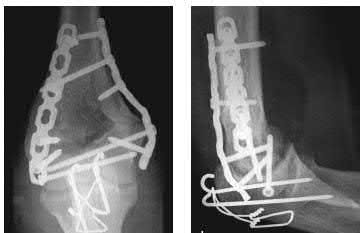

A 28-year-old male sustains a closed comminuted tibial shaft fracture.

Two hours post-injury, he develops severe leg pain unyielding to narcotics. His blood pressure is 120/80 mmHg. Intracompartmental pressure monitoring is performed. Based on current guidelines, which measurement dictates an emergent 4-compartment fasciotomy?

Explanation

Acute compartment syndrome is classically defined by tissue hypoperfusion. The absolute compartment pressure is less reliable than the differential pressure (Delta P). A Delta P (Diastolic Blood Pressure minus Compartment Pressure) of less than 30 mmHg is an absolute indication for emergency fasciotomy, as capillary perfusion gradient is lost when tissue pressure approaches the diastolic pressure.